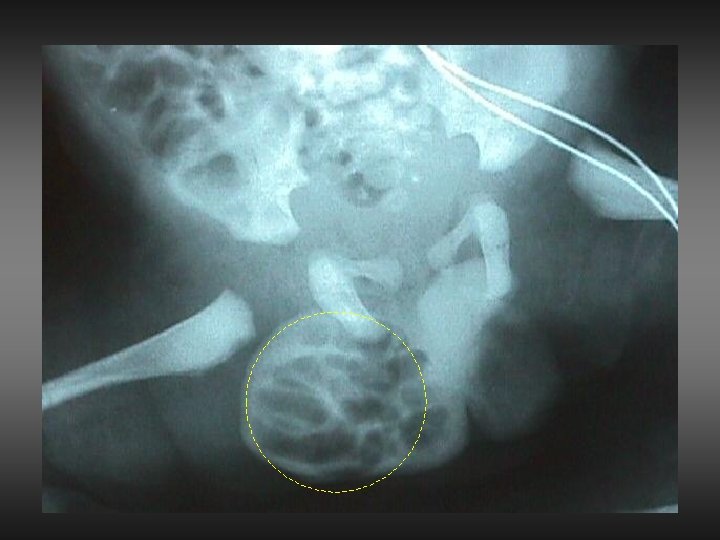

ATASCAMIENTO DAÑO INTESTINAL DAÑO TESTICULAR

MANIOBRAR CON CRITERIO NUNCA ESFUERZO DESMEDIDO PREFERIBLE REDUCIR Y OPERAR 48 hs